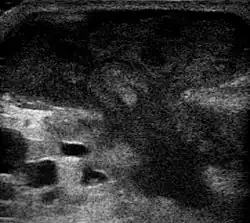

Метод выбора лечения абсцесса брюшной полости — чрескожное дренирование или пункция под контролем УЗИ.

- ↑ UOTW #66 — Ultrasound of the Week. Ultrasound of the Week (7 января 2016). Дата обращения: 27 мая 2017. Архивировано 2 ноября 2016 года.